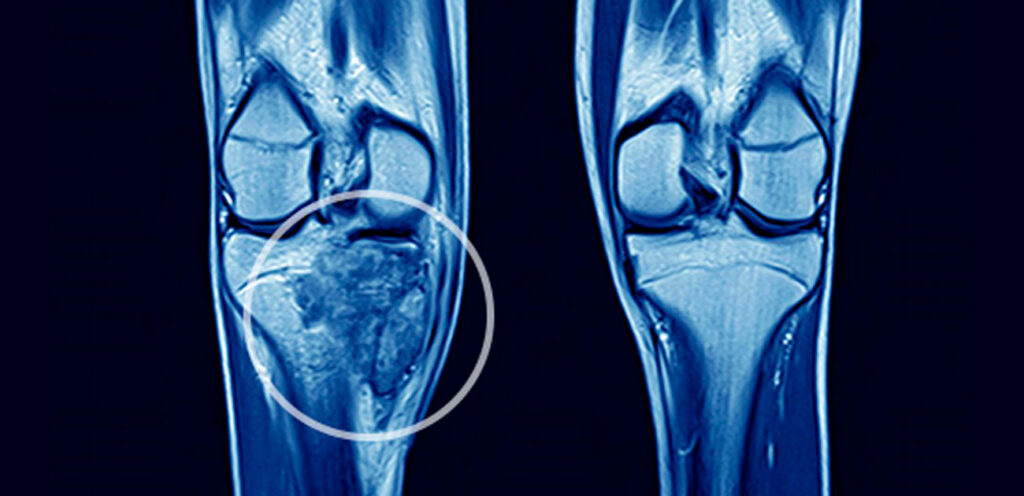

Os tumores ósseos podem ser classificados como benignos ou malignos, e sua origem está relacionada ao crescimento anormal das células que compõem os ossos e a cartilagem. Quando células ósseas escapam do controle normal de proliferação, elas podem formar tumores. Alguns desses tumores são benignos, ou seja, não se espalham para outras partes do corpo, mas outros podem ser malignos, apresentando riscos à saúde.

Por outro lado, o osteossarcoma é um tipo de tumor ósseo maligno e, infelizmente, muito mais grave. O osteossarcoma é caracterizado pela presença de osteoblastos pleomórficos (células de morfologia irregular e variada) e uma alta taxa de mitose, o que indica a divisão rápida e descontrolada dessas células. Este tipo de tumor ósseo ocorre com mais frequência em adolescentes e adultos jovens, e as áreas mais comumente afetadas incluem a extremidade inferior do fêmur e as extremidades superiores da tíbia e do úmero.Embora o osteossarcoma seja raro, ele é um dos tipos de câncer ósseo mais comuns e requer tratamento imediato, geralmente envolvendo uma combinação de cirurgia e quimioterapia.